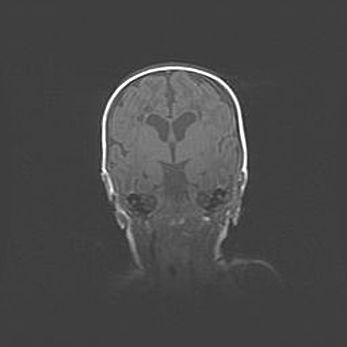

Сообщающаяся гидроцефалия. Кистозная энцефаломаляция головного мозга.

Возраст: 3 месяца 4 дня

Вес: 3100 г

Пол: женский

Окружность головы: 34 см

Срок гестации: 31 неделя

Кистозная энцефаломаляция головного мозга - одна из форм поражения головного мозга в детском возрасте. Характеризуется возникновением множественных и распространённых кист в коре, белом веществе и подкорковых образованиях головного мозга у плодов, новорождённых и детей раннего возраста. Развитие кистозной энцефаломаляции связано с внутриутробной асфиксией и гипотонией, родовой травмой, тромбозом синусов, пороками развития сосудов, инфекциями, сепсисом и другими причинами. Наиболее значимые инфекционные агенты: вирусы простого герпеса, цитомегалии, краснухи, токсоплазмы, энтеробактерии, золотистый стафилококк и другие.